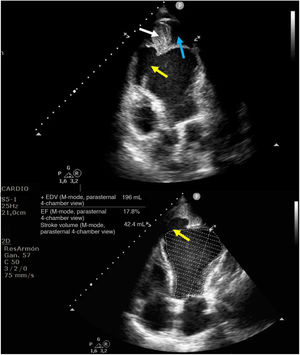

This is the case of a 61-year-old woman who had a myocardial infarction one month prior and subsequently developed post-infarction mechanical complications. The echocardiogram revealed the presence of a large apical pseudoaneurysm (Figs. 1 and 3: blue arrow) (Appendix A Video), with a 2.93cm neck (Figs. 1 and 2: yellow arrow) and free flow of echocontrast through it (Fig. 2: red arrow). The lumen was partially thrombosed (Figs. 1 and 3: white arrow). She also exhibited severe left ventricular dilatation and very severe global systolic dysfunction (Fig. 1) (LVEF 11%; LVOT VTI 7cm). Forty-eight hours after admission, the patient developed SCAI C-D cardiogenic shock, requiring mechanical support with V-A ECMO and an intra-aortic balloon pump, which led to a significant improvement in organ perfusion. After coordination with the referral hospital, she underwent a code 0 heart transplant, with a favorable recovery. This case highlights the importance of echocardiographic diagnosis and mechanical support management in critical situations of cardiogenic shock.